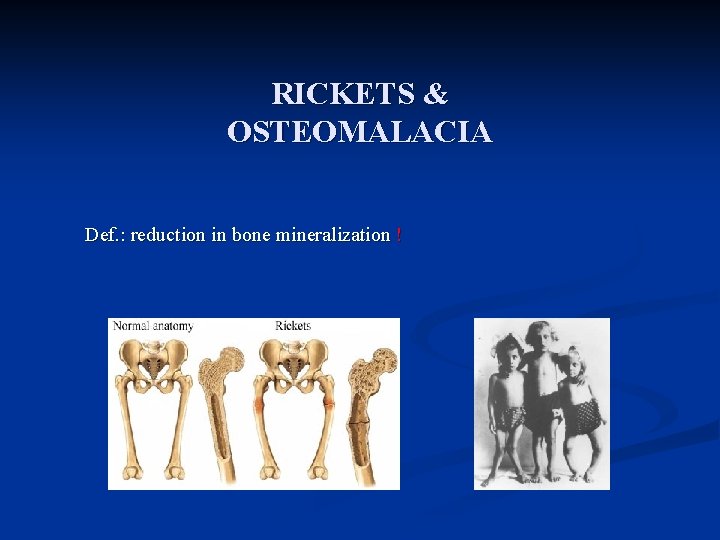

RICKETS & OSTEOMALACIA Def. : reduction in bone mineralization !

OSTEOMALACIA and RICKETS Clinical syndromes that result from inadequate bone mineralization

RICKETS, OSTEOMALACIA PATHOLOGY: Sufficient osteoid, poor mineralization (Rickets is found only in children prior to the closure of the growth plates, while OSTEOMALACIA occurs in persons of any age. Any child with rickets also has osteomalacia, while the reverse is not necessarily true).

Introduction n Normal bone growth & mineralization require adequate availability of calcium & phosphate. n Deficient mineralization can result in rickets and/or osteomalacia. n Rickets refers to the changes caused by deficient mineralization at the growth plate. n Osteomalacia refers to impaired mineralization of the bone matrix. n Rickets & osteomalacia usually occur together as long as the growth plates are open; only osteomalacia occurs after the growth plates have fused.

What are osteomalacia / Rickets Osteomalacia n Disorder of mature bone in which mineralisation of new osteoid bone is inadequate or delayed Rickets n Disease of growing bones in which defective mineralisation occurs in both bone and cartilage of epiphyseal growth plate, associated with: n n Growth retardation Skeletal deformities